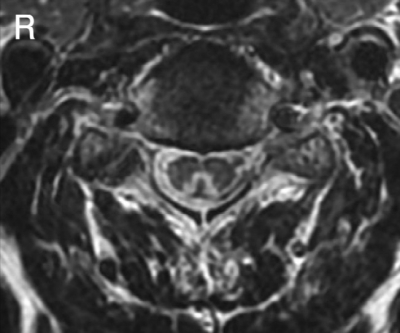

血液所見:赤血球 250万、Hb 9.4 g/dL、Ht 28%、白血球4,400、血小板8.7万。血液生化学所見:総蛋白 7.2 g/dL、アルブミン 4.4 g/dL、 総ビリルビン 1.5 mg/dL、AST 25 U/L、ALT 20 U/L、LD 332 U/L (基準176〜353)、γ-GTP 13 U/L(基準 8〜50)、CK 48 U/L(基準 30〜140)、尿素窒素 23 mg/dL、クレアチニン 0.7 mg/dL、尿酸 5.1 mg/dL、血糖 103 mg/dL、総コレステロール 170 mg/dL、トリグリセリド 72 mg/dL、Na 138 mEq/L、K 5.0 mEq/L、Cl 101 mEq/L、ビタミンB12 75 pg/mL (基準 250〜950)、CEA 2.0 ng/mL(基準 5.0以下)、CA19-9 2.3 U/mL (基準 37以下)。CRP 0.1 mg/dL。頸椎MRIのT2強調像を示す。